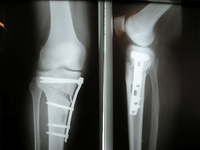

Umstellungsosteotomien, Achskorrekturen

Die Umstellungsosteotomie dient der Wiederherstellung einer geraden Beinachse zur Vermeidung einer Arthrose oder Entlastung von bereits geschädigten Gelenkanteilen.

Sie ist ein operativer Eingriff, der eine krankhaft schräge Beinachse ausgleicht, indem Teile des gelenknahen Knochens je nach Technik entfernt oder eingefügt werden. Übermäßig schräge Beinachsen, wie zum Beispiel die fortgeschrittene O-Bein- oder X-Bein-Fehlstellung (Varus- oder Valgusdeformität), führen zu einer einseitigen Abnutzung des Gelenkknorpels, wodurch starke Schmerzen entstehen können.

Ist der Knorpel bereits großflächig geschädigt oder liegt eine Schädigung auch in anderen Knieglenksabschnitten vor, ist von einer Umstellungsoperation jedoch abzuraten.

Bei der Umstellungsosteotomie wird der gelenknahe Schienbein- oder Oberschenkelknochen durchtrennt und je nach Art der Achsabweichung mit einem körpereigenen Knochenkeil (z.B. Beckenknochen) abgestützt oder aber es wird ein Keil entnommen. Damit der Knochenspalt wieder zuheilt, muss der Knochen mit einer Platte und Schrauben stabilisiert werden. Nach der Ausheilungsphase sollte das eingebrachte Material in einer zweiten Operation ggfs. wieder entfernt werden.